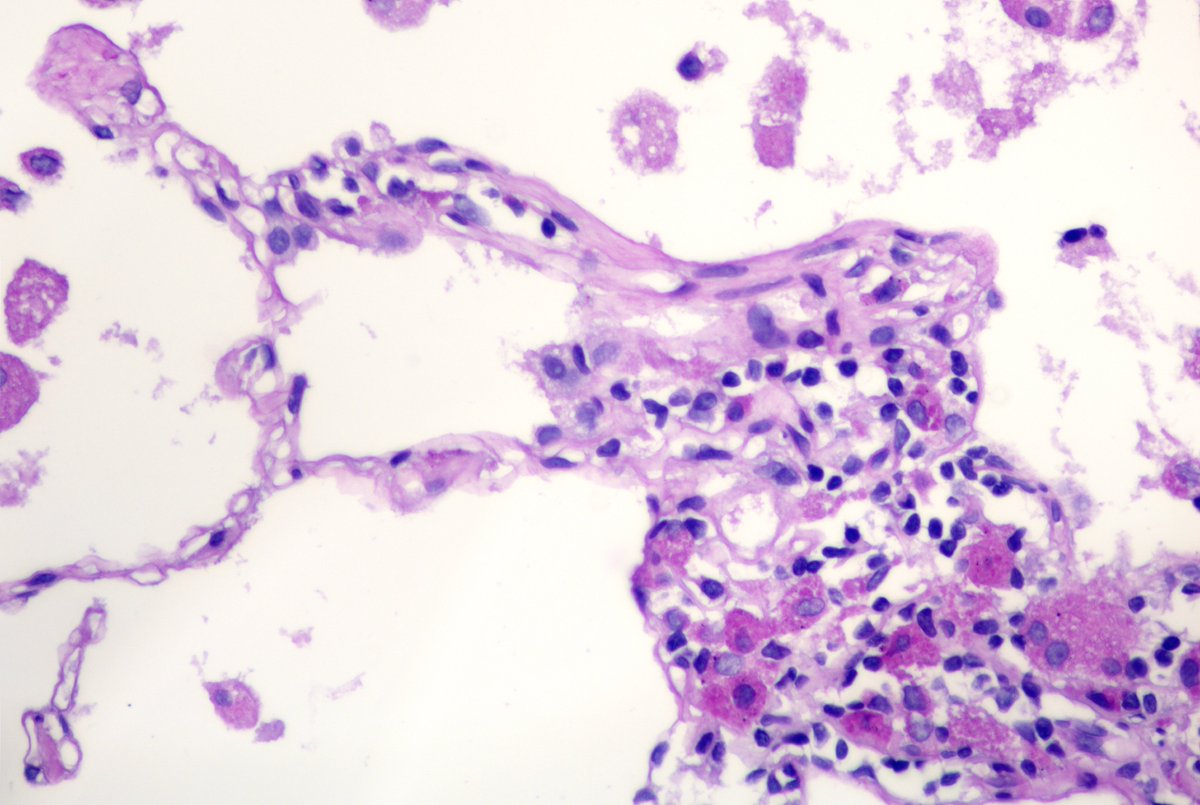

F40y,chronic cavitary pulmonary aspergillosis, atypical resection of the low lobe of the lung.

several cavities with a fungal ball, granulation tissue, chronic inflamation, metaplastic squamous epithelium, calcium oxalate crystals